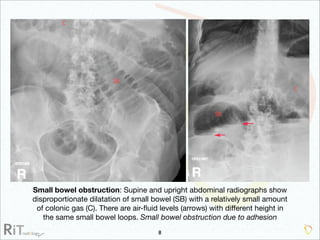

The document discusses the imaging modalities used in evaluating acute abdominal pain, including radiography, ultrasound, computed tomography (CT), and scintigraphy, highlighting their roles, indications, and limitations. It emphasizes the complexity of diagnosing acute abdomen due to its broad differential diagnoses and the necessity for accurate imaging to inform timely management. Additionally, the document outlines considerations such as patient history, contrast medium reactions, and appropriate imaging criteria based on various clinical presentations.